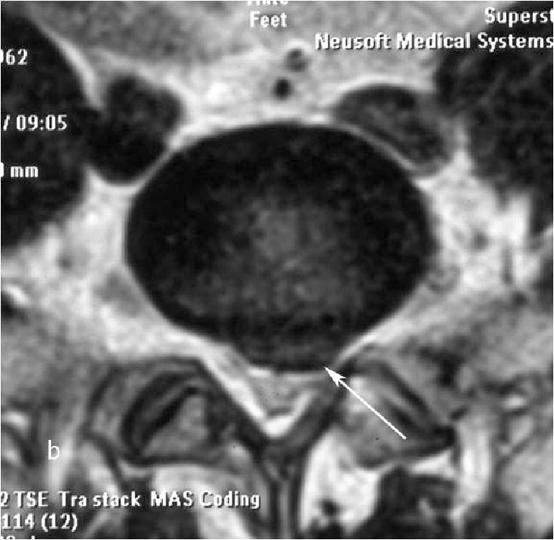

При рентгенографии (Рис.7) и МРТ (Рис.8) поясничного отдела позвоночника выявляется дегенеративный ретролистез L5 позвонка, секвестрированная  парамедианная грыжа мп диска L5-S1  слева.

Рис. 9a. Магнитно-резонансная томография (МРТ) поясничного отдела позвоночника в сагиттальной (a) и аксиальной  (b) проекции. Стрелкой показана мп секвестрированная парамедианная грыжа диска L5-S1 слева. Рис. 9b. Магнитно-резонансная томография (МРТ) поясничного отдела позвоночника в сагиттальной (a) и аксиальной  (b) проекции. Стрелкой показана мп секвестрированная парамедианная грыжа диска L5-S1 слева.

Рис. 8a,b. Магнитно-резонансная томография (МРТ) поясничного отдела позвоночника в сагиттальной (a) и аксиальной (b) проекции. Стрелкой показана мп секвестрированная парамедианная грыжа диска L5-S1 слева.